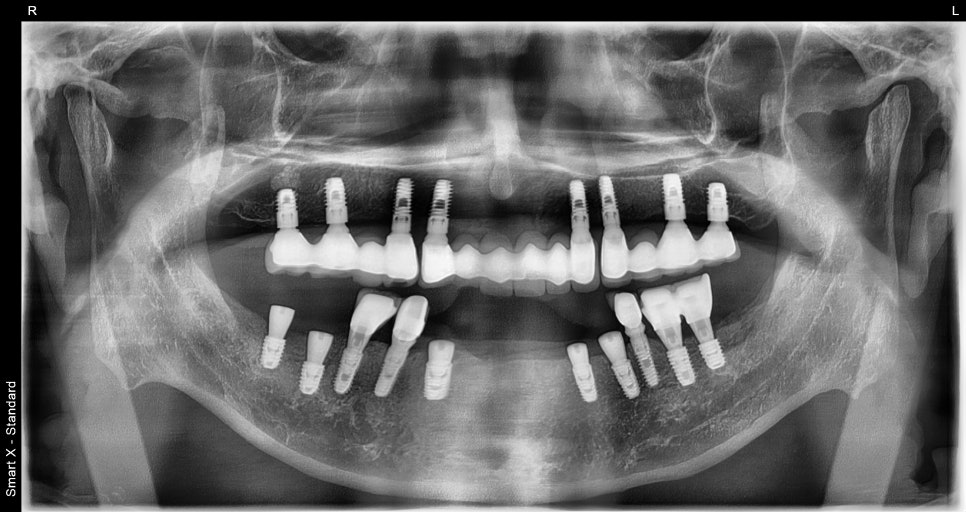

Left photo: A panoramic X-ray taken before treatment. A fractured implant is visible in the lower jaw, and the condition of the existing implant prosthesis can be seen in the upper jaw.

Left photo: Most of the upper teeth had implant prostheses, but the screw access holes were open and needed repair.

Right photo: The lower teeth had a missing crown and a broken implant, so overall reconstruction was needed.